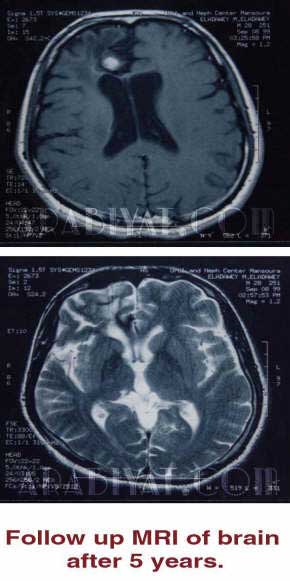

ماذا عن الحالة التي قمتم بتطبيق العلاج عليها ؟ في عام 94م تم تحويل أحد المرضى لي مصحوباً بأشعة مقطعية على المخ تشير إلى وجود ورم كبير بحجم البرتقالة تقريباً بالفص الأمامي للمخ ثبت أنها ورم سرطاني وقد رفض المريض الخضوع للعلاج الإشعاعي أو الكيميائي فحصلت على الموافقة لوضع 3 سم من العسل ولقاحه مكان الجرح وتكرر ذلك إلى أن تم إجراء أشعة على المخ للمتابعة فتبين أن الورم السرطاني قد انكمش واستمر العلاج لشهور شهدت تقدماً مطرداً تبعها إجراء أشعة دورياً وأخيراً بعد خمس سنوات خرجت النتائج النهائية تؤكد اختفاء الورم وتبين عدم وجود أي ارتجاع له ، وقد اصطحبت المريض الذي كتب الله له الشفاء بهذا العلاج إلى المؤتمر الطبي الخاص بجراحة المخ والأعصاب لشرح التجربة كاملة وهو بالمناسبة يمارس اليوم حياته بشكل طبيعي . إذن لماذا لم يتم الاعتراف بهذا العلاج واعتماده كبديل للعلاج الكيميائي والإشعاعي والجراحي ؟ البحث العلمي لايزال بحاجة لاستكمال بعض النقاط البحثية على مستوى البيولوجية الجزئية حتى يكتمل، واليوم هناك رؤوس مواضيع بحثية مفتوحة في جميع مراكز البحوث للبحث عن علاج جديد للسرطان معتمدين على ما يسمى بالجزئية الحيوية والجزئية السرطانية... لذلك أوجه ندائي لمراكز البحوث العربية والإسلامية لدعم هذا البحث الذي يتناول علاج الأورام السرطانية ببروتينات عسل النحل، فمن العار أن ينجزه أو يتممه شخص أو مركز غير عربي وغير مسلم وأعتقد أننا كمسلمين قد جاء الدور علينا الآن لكي ندلو بدلونا ونقدم شيئاً جديداً في هذا المضمار فالعلاقة بين المسلمين والقيمة العلاجية لعسل النحل معروفة وبإثبات قدرتها على علاج أخطر أمراض العصر سنقدم إعجازاً طبياً جديداً في القرآن قد يهز العالم الذي لايزال يحبو في أبحاث الجزئية الحيوية ويعاني تحت وطأة الأعراض الجانبية للعلاج الكيميائي والإشعاعي الذي يأخذ معه الكثير ولايزر إلا القليل . يبدو أن هذا البحث بقي عالقاً عند مرحلة معينة ولسنوات عديدة فماهو السبب ؟ وهل لدى مراكز البحث المحلية أو العالمية تحفظ علمي على تبنيه ؟ فعلا الموضوع شبه متوقف عن أى إضافة منذ عام 2000 والمشكلة في عدم وجود الدعم المادي أو المعنوي ... فقد قدمت شيئاً عندما كنت قادراً على ذلك بحدود إمكانياتي الشخصية... وعندما انتهت مواردي توقف كل شئ... كنت أراهن على أنه بعد نجاح الخطوة الأولى وتقديمها وقبولها عالمياً لابد وأن أجد الدعم داخل عالمنا العربي والإسلامي خاصة وأن مشروع بحثي, نتائجه الأولى مبشرة و تم قبول الفكرة في 3 او4 مؤتمرات عالمية لم يرد في أي منها تحفظات من أى نوع علماً أن اللجان العلمية لهذه المؤتمرات هم مدراء وأعضاء أكبر المراكز البحثية العالمية.... وكل ما ينقصنا هو الإمكانيات . هل لك أن تذكر لنا تلك المؤتمرات ؟ هذا البحث تم تقديمه وقبوله في 4 مؤتمرات علمية عالمية هي : ـ المؤتمر العالمي الثالث عشر لأبحاث أورام المخ وعلاجها, اليابان أكتوبر 1999. ـ المؤتمر الآسيوي الاسترالي العاشر لجراحي المخ والأعصاب, لاهور نوفمبر 1999. ـ المؤتمر الأوربي الرابع لأورام الجهاز العصبي, كوبنهاجن يونيو 2000. ـ المؤتمر العالمي الثالث ( جليوما من الجينات وحتى العلاج ) أمستردام ابريل 2001. أضفت العديد من التفاصيل عن المشروع البحثي في منتدى عربيات وقد تابعنا ذلك ووجدنا تفاعل كبير من قبل القراء ورواد الموقع فكيف بدأت علاقتك بالمنتدى ؟ بالنسبة لمعرفتى بمنتدى عربيات فقد جاءت مصادفة أثناء استخدامي لمحركات البحث على الإنترنت فوجدت اسمي في المنتدى وانتقلت للرابط لأجد موضوع البحث المنشور بمجلة الأهرام العربي مطروحاً للنقاش, وتفاعلت مع ذلك مضيفاً بعض المداخلات ومشيراً إلى أن البحث يحتاج للدعم حتى يتم استكماله واعتماد العلاج... ومع تبني إحدى الأخوات الفضليات لحملة داعمة للبحث قمت بإدراج بعض الخطوات المطلوبة في هذا الإطار ودراسات للجدوى الإقتصادية منه للجهات الداعمة . هل بالإمكان تحديد وسائل الدعم المطلوبة لإتمام البحث ؟ الأولى أن توجد في أي دولة عربية أو إسلامية إمكانيات وكوادر تعمل في مجال الجزئية الحيوية وفي هذه الحالة كل ما أطلبه هو أن يتم دعوتي للعمل المشترك لنشر ورقتين علميتين تحملان اسمي واسم كل من سيشارك فيها . والثانية في حال عدم وجود تلك الإمكانات لدينا فان هناك عرض من جامعة ماكجيل/ كندا لعمل رسالة دكتورة حيث توجد تلك الإمكانيات بكفاءة عالية ولكنهم اشترطوا وجود دعم مادي لفترة تواجدي هناك ( ثلاث سنوات ) وهو ما عجزت عنه. ماذا عن الجدوى الاقتصادية التي يمكن أن تعود على الجهة الداعمة ؟ من المعروف أن شركات الدواء تعتبر من أكثر الشركات ربحية في العالم ولكننا نعتبر مجرد سوق لمنتجاتها حيث لاتقيم أي مراكز أبحاث حقيقية في بلادنا لاستنباط أدوية أو جزيئات علاجية جديدة خشية من أن نفهم ( الفولة ) كما يقال ونبدأ بمنافستها... ولعلنا نتعجب عندما نعلم أن عدد كبير من كوادرنا وعلمائنا والباحثين بتلك الشركات العالمية هم من أبنائنا... ومع حقوق الملكية الفكرية التي أصبحت تقض مضاجع القائمين على شركات صناعة الدواء العربية والتي يقتصر دورها على شراء المواد الخام وتعبئتها وطرحها في الأسواق تحت أسماء جديدة لن يصبح لذلك الإنتاج قيمة لأنه يبقى وفق قوانين الملكية الفكرية الجديدة من حق الشركة المكتشفة للجزيء الفعال ولن تتمكن الشركات العربية من استخدامه إلا بعد مرور عشرات السنين يكون خلالها قد انتهى دوره وظهر دواء أحدث أو أنها تصبح بحاجة لتصريح من الشركة المكتشفة والتي ستفرض شروطها... فعلى القائمين على شركات الدواء الوطنية إدراك أنه لابد من وجود مراكز أبحاث حقيقية لاستنباط أدوية جديدة داخل مصانعنا وبالطبع يمكن لأى من هذه الشركات أن تعتبر هذا المشروع نواة لإنشاء مركز أبحاث للجزئية الحيوية والسرطانية ولاكتشاف أدوية جديدة والدخول في المنافسة العالمية تفادياً للسقوط عند تطبيق اتفاقية الجات . |

النتائج المعملية الأولية وحالة مريض شفى تماما من أسوء أنواع سرطان المخ باستخدام هذه الوسيلة فقط - وان تمت بصورة اولية فى ذلك الوقت- دون استخدام أى علاج كيميائي أو إشعاعي أو خلافه ولايزال حيا يرزق حتى تاريخه و بعد أكثر من 10 سنوات على علاجه.